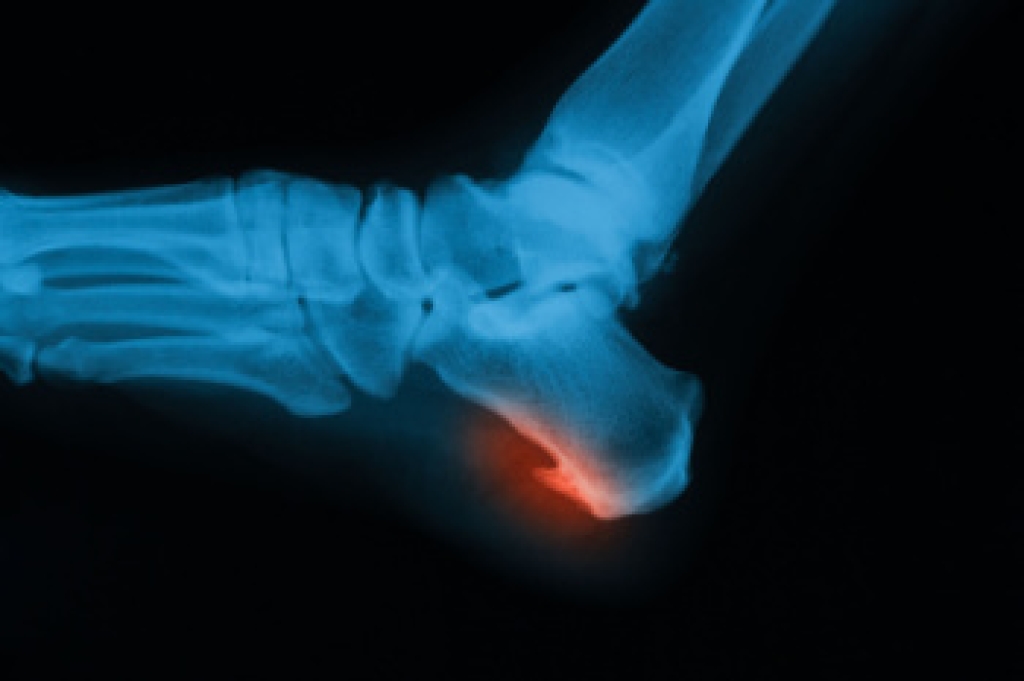

Turf toe is a sprain of the ligaments surrounding the big toe joint, typically occurring in athletes who play on artificial turf, though it can affect anyone engaged in activities that involve pushing off the big toe forcefully. Turf toe is usually caused by repetitive hyperextension of the big toe, often when an athlete or dancer pushes off the ground. The injury is classified into three grades. Grade 1 involves mild stretching of the ligaments, causing minor pain and swelling. Grade 2 includes partial tearing, leading to moderate pain, bruising, and difficulty in movement. Grade 3 is a complete tear, resulting in severe pain, significant swelling, and joint instability. Symptoms of turf toe include pain, swelling, and limited range of motion in the big toe. Diagnosis is made through a physical exam and imaging studies like X-rays. Treatment varies by grade, ranging from rest for milder cases to immobilization or surgery for severe injuries. If you are suffering with what you think might be turf toe, it is suggested that you consult a podiatrist for a proper diagnosis and treatment.

Foot and ankle injuries are a common occurrence when it comes to athletes of any sport. While many athletes dismiss the initial aches and pains, the truth is that ignoring potential foot and ankle injuries can lead to serious problems. As athletes continue to place pressure and strain the area further, a mild injury can turn into something as serious as a rupture and may lead to a permanent disability. There are many factors that contribute to sports related foot and ankle injuries, which include failure to warm up properly, not providing support or wearing bad footwear. Common injuries and conditions athletes face, including:

Sports related injuries are commonly treated using the RICE method. This includes rest, applying ice to the injured area, compression and elevating the ankle. More serious sprains and injuries may require surgery, which could include arthroscopic and reconstructive surgery. Rehabilitation and therapy may also be required in order to get any recovering athlete to become fully functional again. Any unusual aches and pains an athlete sustains must be evaluated by a licensed, reputable medical professional.